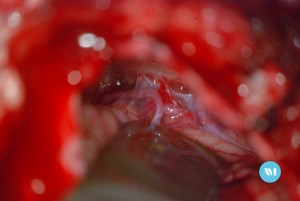

Algunos pacientes pueden requerir cirugía para aliviar la presión sobre el nervio. Las técnicas:

- Cirugía para extirpar un vaso sanguíneo que está ejerciendo presión sobre el nervio trigémino (llamada descompresión microvascular o DMV).